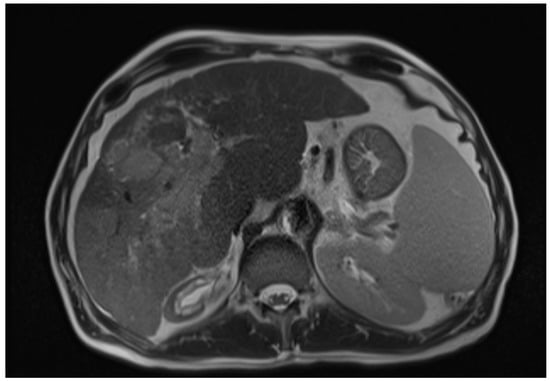

The diagnosis of HCC Is based on a combination of clinical, laboratory, radiographic, and histopathologic features [5]. The imaging diagnosis is based on the detection of the lesion’s vascularity [6]. Advanced imaging techniques, such as contrast-enhanced ultrasound (CEUS) and magnetic resonance imaging (MRI), have shown promising results in detecting and characterising HCC [6]. CEUS utilises microbubble-based contrast agents to provide real-time imaging of the tumour vasculature, allowing for improved lesion detection and differentiation from non-malignant liver lesions. On the other hand, MRI offers multiparametric imaging capabilities, including dynamic contrast-enhanced and diffusion-weighted imaging, enabling better tumour characterisation and assessment of treatment response [6,7] (Figure 1). Moreover, molecular imaging techniques, such as positron emission tomography (PET) using tracers like fluorodeoxyglucose (FDG), have shown potential in assessing HCC metabolic activity and predicting prognosis [6]. Recent advancements in imaging technology have also facilitated the integration of artificial intelligence (AI) algorithms to aid in diagnosing and staging HCC. These AI-based approaches leverage machine learning techniques and large datasets to improve the accuracy and efficiency of HCC diagnosis, allowing for earlier detection and intervention [8].

Figure 1. Axial T2-weighted MRI image of hepatic cirrhosis with HCC [9].